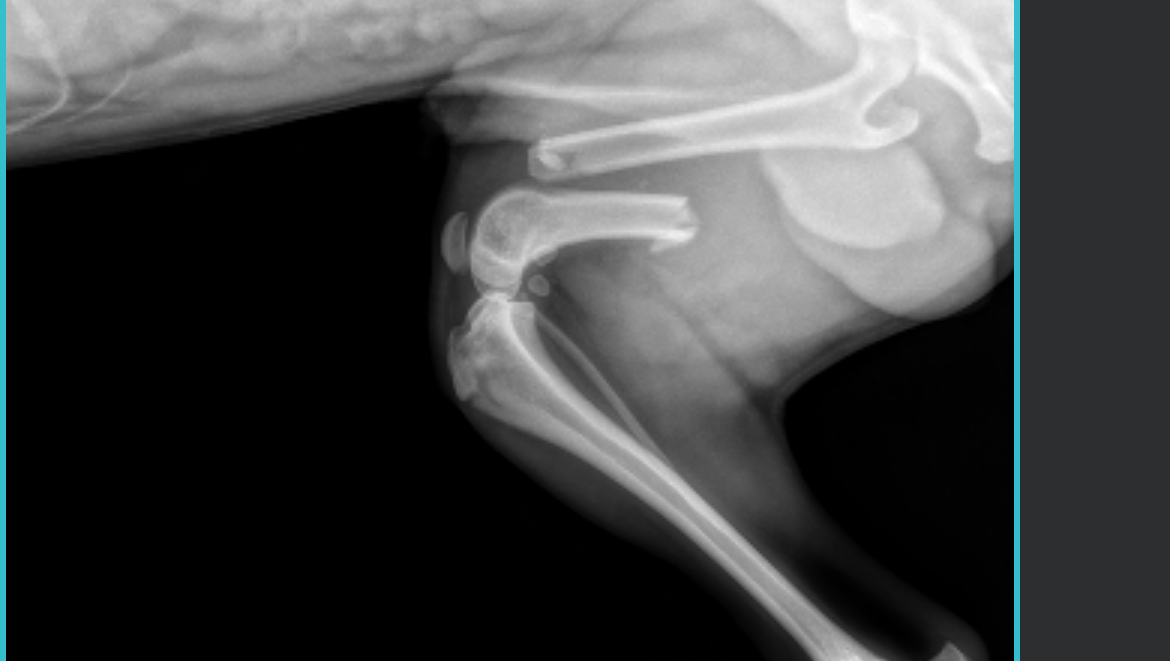

milo was attacked last night and had his femur snapped in half. he needs emergency orthopedic surgery to prevent his hind leg from being amputated.